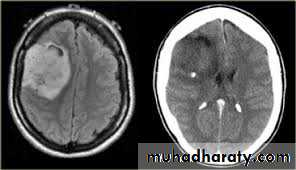

Secondary metastasis

Old age group above 50 Y , any lesion within the cerebellar hemisphere it is secondary metastasis unless proven otherwise F. from breast CA M. from bronchogenic CA .

Appear as nodular single or multiple lesion hypo dense or hyper dense .

Surrounded by per focal edema

Enhanced as solid or ring pattern of enhancement .